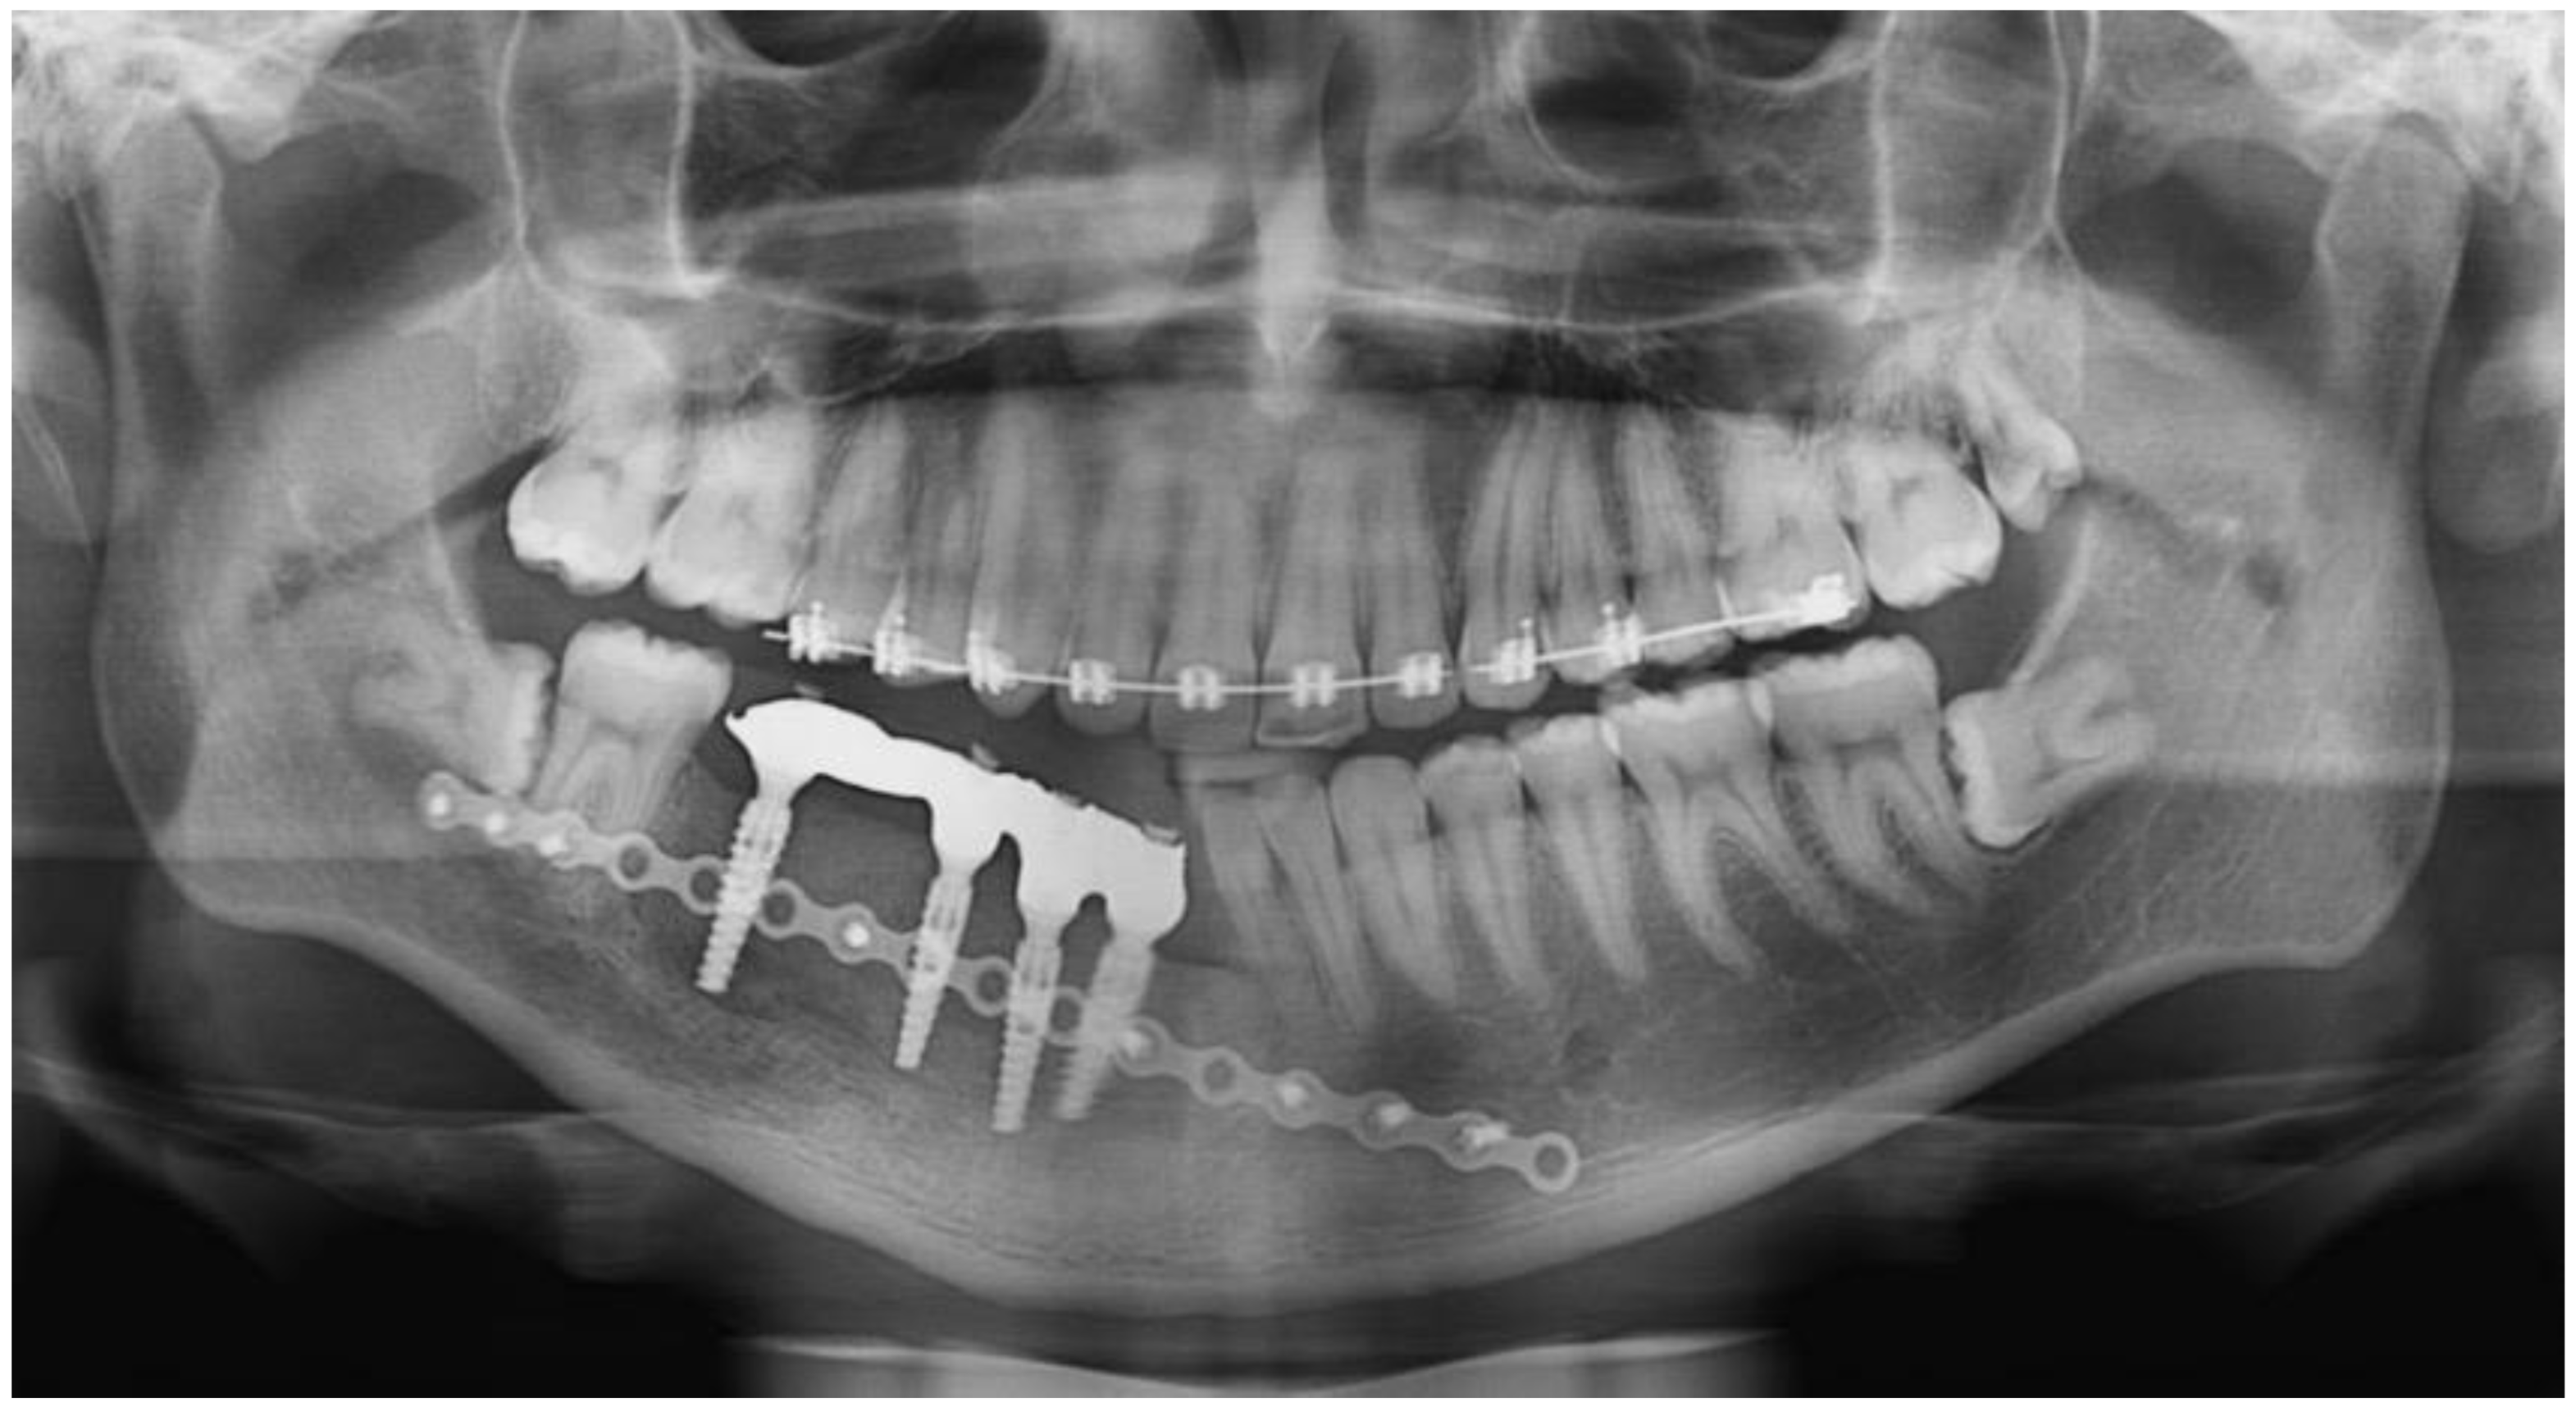

2.1. Case 1

2.2. Case 2